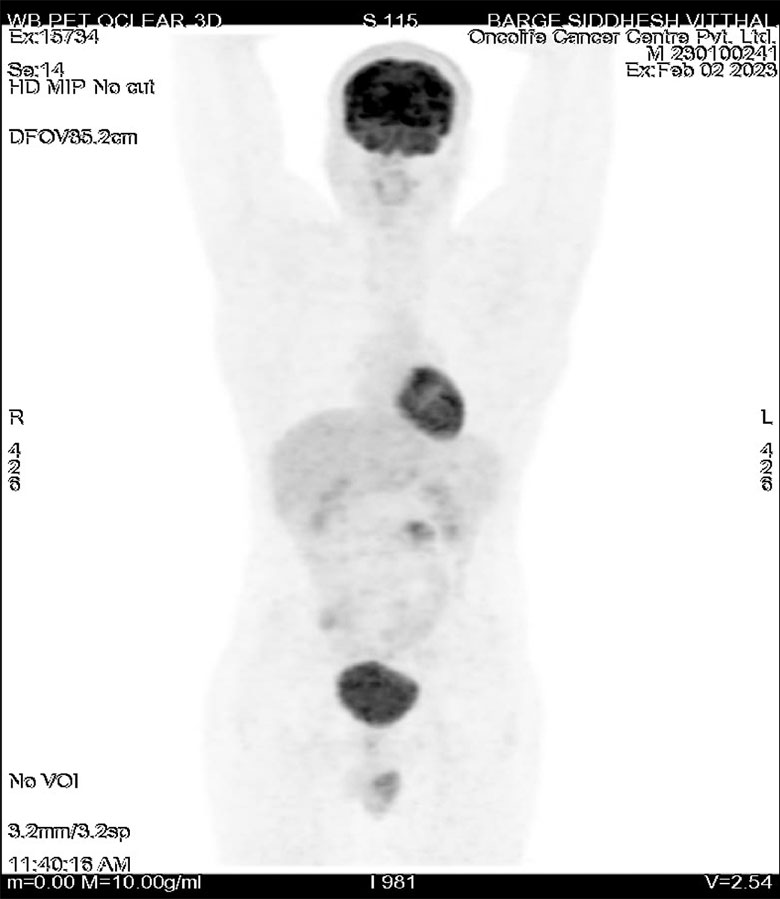

Post chemotherapy PET scan was done on 5/5/2023 s/o

No definite scan evidence of metabolically active residual/recurrent disease at operated site in scrotum on left side. Few necrotic lymph nodes at left paraaortic region, showing mild metabolism – residual metastatic disease. No other hypermetabolic malignant lesions elsewhere in the body. As compared to previous PET CT report dated 02/02/2023, left testis lesion is not visualised (postop status. There are significant decrease in size and metabolic activity of left paraaortic lymph node.